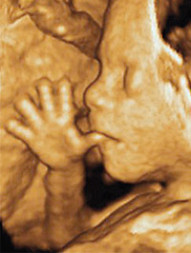

Przed urodzeniem rozwój człowieka w macicy matki odbywa się w sposób ciągły, pojawiają się w określonym czasie organy: mózg, płuca, serce, nogi i ręce. W sposób umowny embriolodzy dzielą ten czas na okresy zarodkowy i płodowy rozwoju dziecka. Dzisiaj zajmiemy się okresem zarodkowym, embrionalnym. Cz